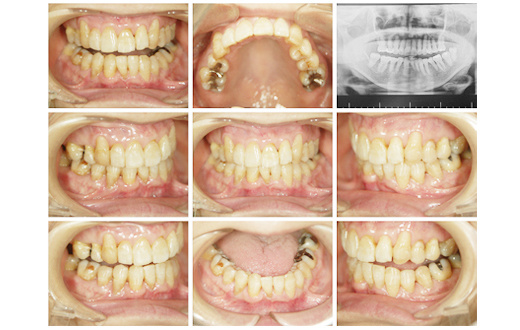

症例1

女性 61才 1年5カ月